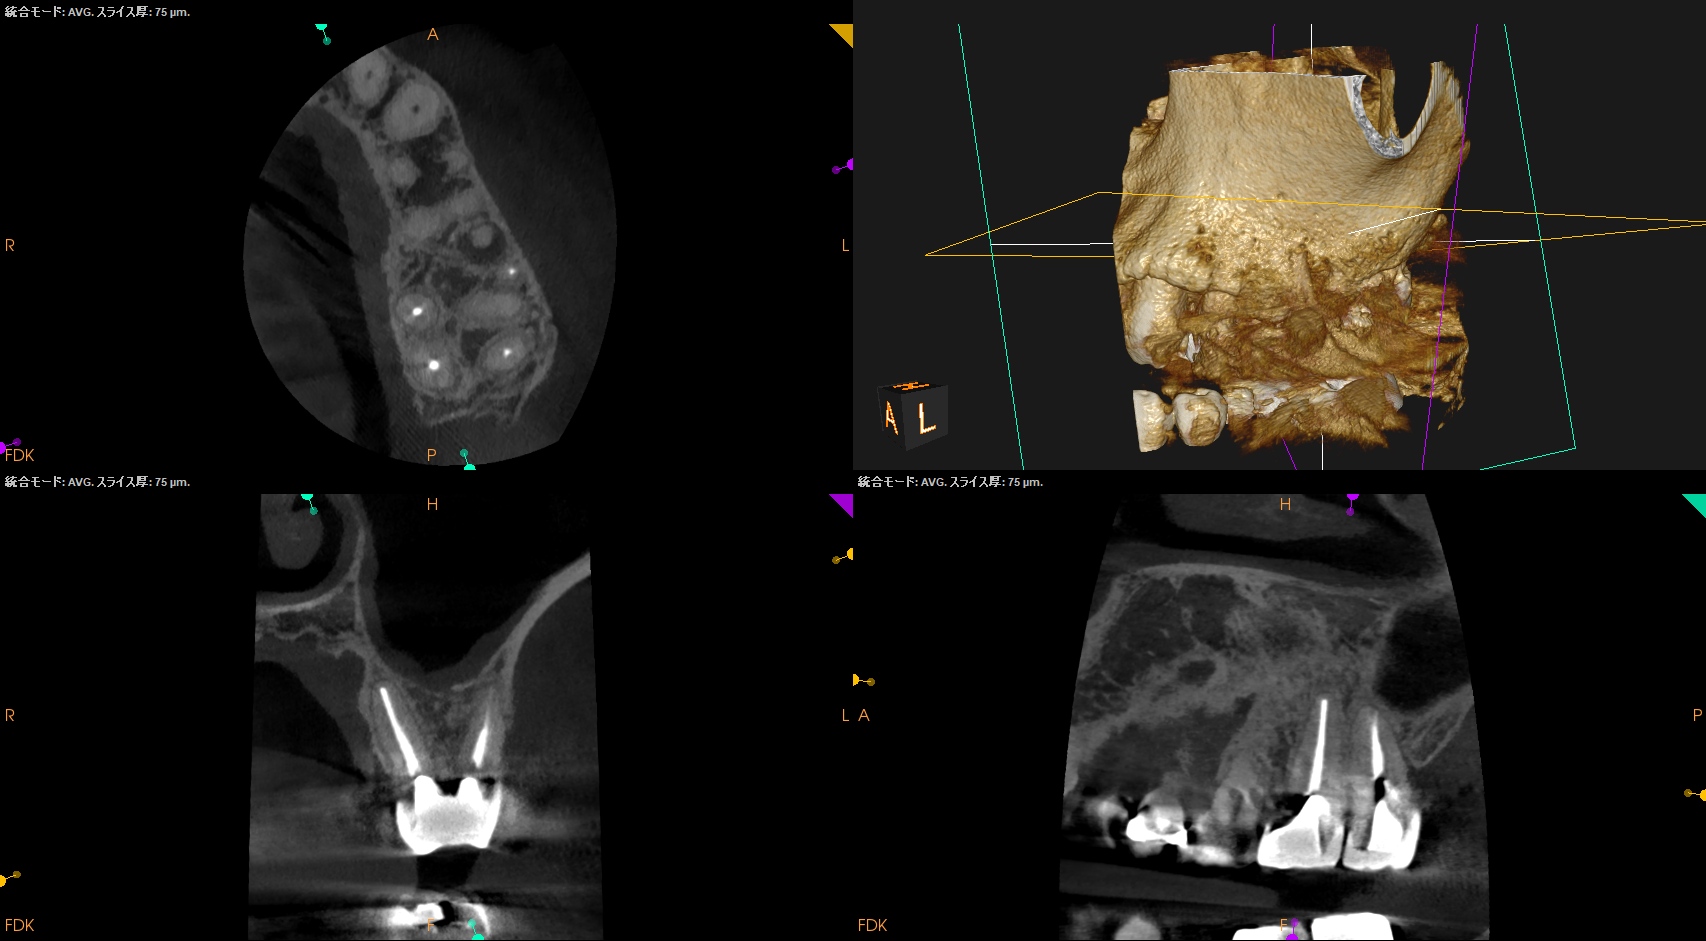

CBCTから当該Apex相当部位を確認しOsteotomyしてRoot resectionし、メチレンブルーで染色した。

その時の絵がCBCTでMBを3mmで切断した

この絵と相似形なので問題はないと考えた。